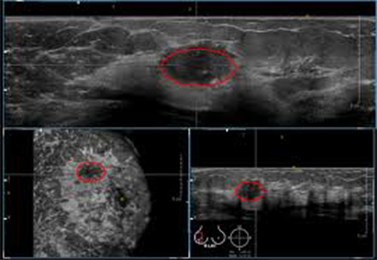

• Surface mode: Για την απεικόνιση τοιχωματικών ανωμαλιών (πολύποδες ενδομητρίου, υπενδομήτρια άλως, μορφώματα ωοθηκών και μαστών).

• Transparent max/min: Για την ανίχνευση της σύστασης των όγκων (αποτιτανώσεις, κυστικά στοιχεία).

• Niche aspect: Για την πληρέστερη ανάλυση της δομής-σύνθεσης του όγκου του σώματος της μήτρας, των ωοθηκών και των μαστών.

• Tomographic Ultrasound Imaging (ΤUI): Παρέχει απεριόριστη δυνατότητα στο να συλλέγει αξιόπιστες πληροφορίες για την απεικόνιση ανωμαλιών σε συγκεκριμένες περιοχές.

Η διαδικασία της λεπτομερειακής μελέτης του σώματος της μήτρας, των ωοθηκών και του μαστού, χρησιμοποιεί ηχητικά στοιχεία για να καθορίσει περιοχές που θεωρούνται τμήμα μιας συγκεκριμένης δομής. Έτσι αναγνωρίζονται μορφολογικά χαρακτηριστικά της παθολογίας για παράδειγμα η παρουσία υγρού εντός της ενδομητρικής κοιλότητας, παρουσία ηχογενών δομών που προβάλουν μέσα στην ενδομητρική κοιλότητα ή συμπαγούς βλάβης που καταλαμβάνει την ενδομητρική κοιλότητα, η τις ωοθήκες η τούς μαστούς και ελέγχεται πληρέστερα η εξωτερική επιφάνεια και η παρυφή των νεοπλασμάτων και οριοθετείται η σχέση τους με παρακείμενους ιστούς και όργανα.